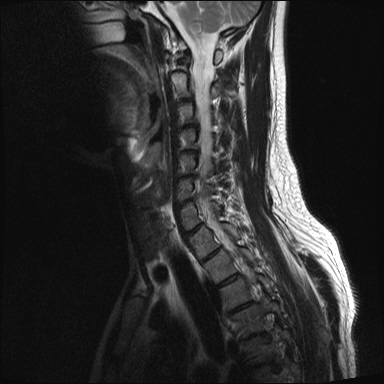

ȸ ϸ鼭 ۼ Դϴ. Ű 172 72 35 ˰Ե ͳ õ ijħ ǥغ ϱ ȣϽ 1C.ڵӸ 1C.ٸǷ 1C.ټ Ǹ 1C.ٱ () 1C.߷ () 1C.Ƿ () 2C.ھȱ, 2C.ڴ 2C.ھ˷⼺(˷) ḷ 2C.ٴ, 2C.ٰḷ 2C., 2C.ٺ, 2C.ٸ 2C.پ˷⼺(˷) 3C.ġ Ű 3C. 4C. 6C.ڸ 6C.ھ Ḳ 6C.ڻ 1T.ȣ 4T. 3T.ȯ, 5T.ȯ ҷ, 6T.ټ 6T.ٽƮ 9T.˷ 10T.ٸǷ 2L. 㰡 2L.ȣ 3L. 3L.ڹ 4L.° 4L.ھƷ 4L.ڿ, 4L.ڵ Ʒ 5L.ڴٸ Ʒκ̳ 5L.ڹ߸̳ õ().¦ٸ ()ũ( ߰Ż) Ը Ͽ ũ(߰Ż), ũ(߰Ż)ġ, , Ḳ , , Ḳ ġ ȱ ǰϰų ڸ, , ڰ , , Ǵ ġ ô ¦ٸ(ٸ̰ ٸ) , 㸮 ̳ ġ Ƹ ġ ħ ߷, , нɷ 帶, ɱٰ, ɺ ڸǥغ ǥغ ϰ ߴ ġ 1. ũ 1) ߺñ: 1 Ӹ ־ ʹ 2)˻ : ** x-ray MRI Ȯ 3,4,5 ũ ̸, Ư 4 ũ ¦ Ƣ . 3)ġ: Ű漺 , ġḦ ʾҰ, Ư ǿ ħ °, Ȱġ(Ȳ,ħ, ȸ ) . 4)ġ : 1.Ͻ ȿ ־, ð 2. 㸮() 1) ߺñ: 3 ϱ ٳѱ⸦ ڱ 㸮 , ģ ƮĪ شٸ 㸮 ȭ ƮĪ Ʋ . 2)˻ : ǿ 㸮 ġ . 3)ġ: ħ ȰġḦ 4)ġ :Ͻ ȿ ־ ɰų 㸮 3. ڰ 1) ߺñ: ڰ̰ ִ Ȯ 5 Ǵܵ 2)˻ : 6~7ð 2~3ð ڸ , ȣ 3)ġ: ġḦ ް , ڰ *** ߿ Ƽ ϰ 4)ġ : ڸ 4. 1) ߺñ: 2~3 ְų Ͻ ־ 2)˻ : ˻縦 ʾ, ʰ ô ó 3)ġ: 4)ġ : 5. ô 1) ߺñ: 3 ڿ ɾƼ ٸ µ ٸ ª 2)˻ : 7 Ȱ X-RAY ణ ô ִٰ Ǹ 3)ġ: ġ 4)ġ : Ͻ 6. (˷ ḷ) ȱ 1) ߺ: 5 2)˻ : Ű 3)ġ:1~2 ѹ ް Ⱦ ֱ ְ 4)ġ : , ħħϰų 7. , Ѽ ȣ ߺñ: ɸ Բ ڰⰡ , ڸ, ä, 2)˻ : Ḧ ʾ, ڰ Ⱑ ư, Ѽ Ҵ Ȳ µ ϰ ȸ ȭ ˷ֽ ǥغ ϴ ڸ ϴ. 㿡 ħ ȸԲ ˷ֽ Ư ġü ġὺƮĪ Բ ġ ȭ ʰ ȸǴ ڼ ϴ ϴ. ˷ֽ ͵ ̳ ǰ ͳݿ ִ ٸ Դϴ. ϴ ȭ Ÿϴ. ϴ. پٰ ϴ. ϴ پų ϴ. 30и 30 ̻ ϶ ϼ̽ϴ. 30иٴ ϰ ҷ ߽ϴ. Ȳ ٷ ϴٰ ٽ ϴ. ķ 鵵 Ÿϴ. γ ȸԲ ڵȽϴ. ٽ ȭּż Ȳ ϰ ʰ ּ̰ ڼ ణ ߸ϰ ־ ֽð ʰ ˷ּ̽ϴ. ȭ Ŀ ߰ ȭ ߾ ߴµ ϴٰ 1 ȭ ѹ ʾҾϴ. ˷ֽ ˷ֽ 뿡 ణ ̴ ε ̼ϰ ٸ ̷ Դϴ. ʰ ϴ ڼ ü ٽ ϰ ˷ּ̰ а ߴص ϰ ˷ֽ θ ϶ ϼ̽ϴ. ˷ֽŵ Ȱ ϰ غ ı øڽϴ. ȸ 㵵 ű Դϴ. ۼ ıԴϴ. http://najari.kr/Board/index.php?Code=free1&No=5141&action=View&st=&sn=&sc=&Keyword=&Page=1 |